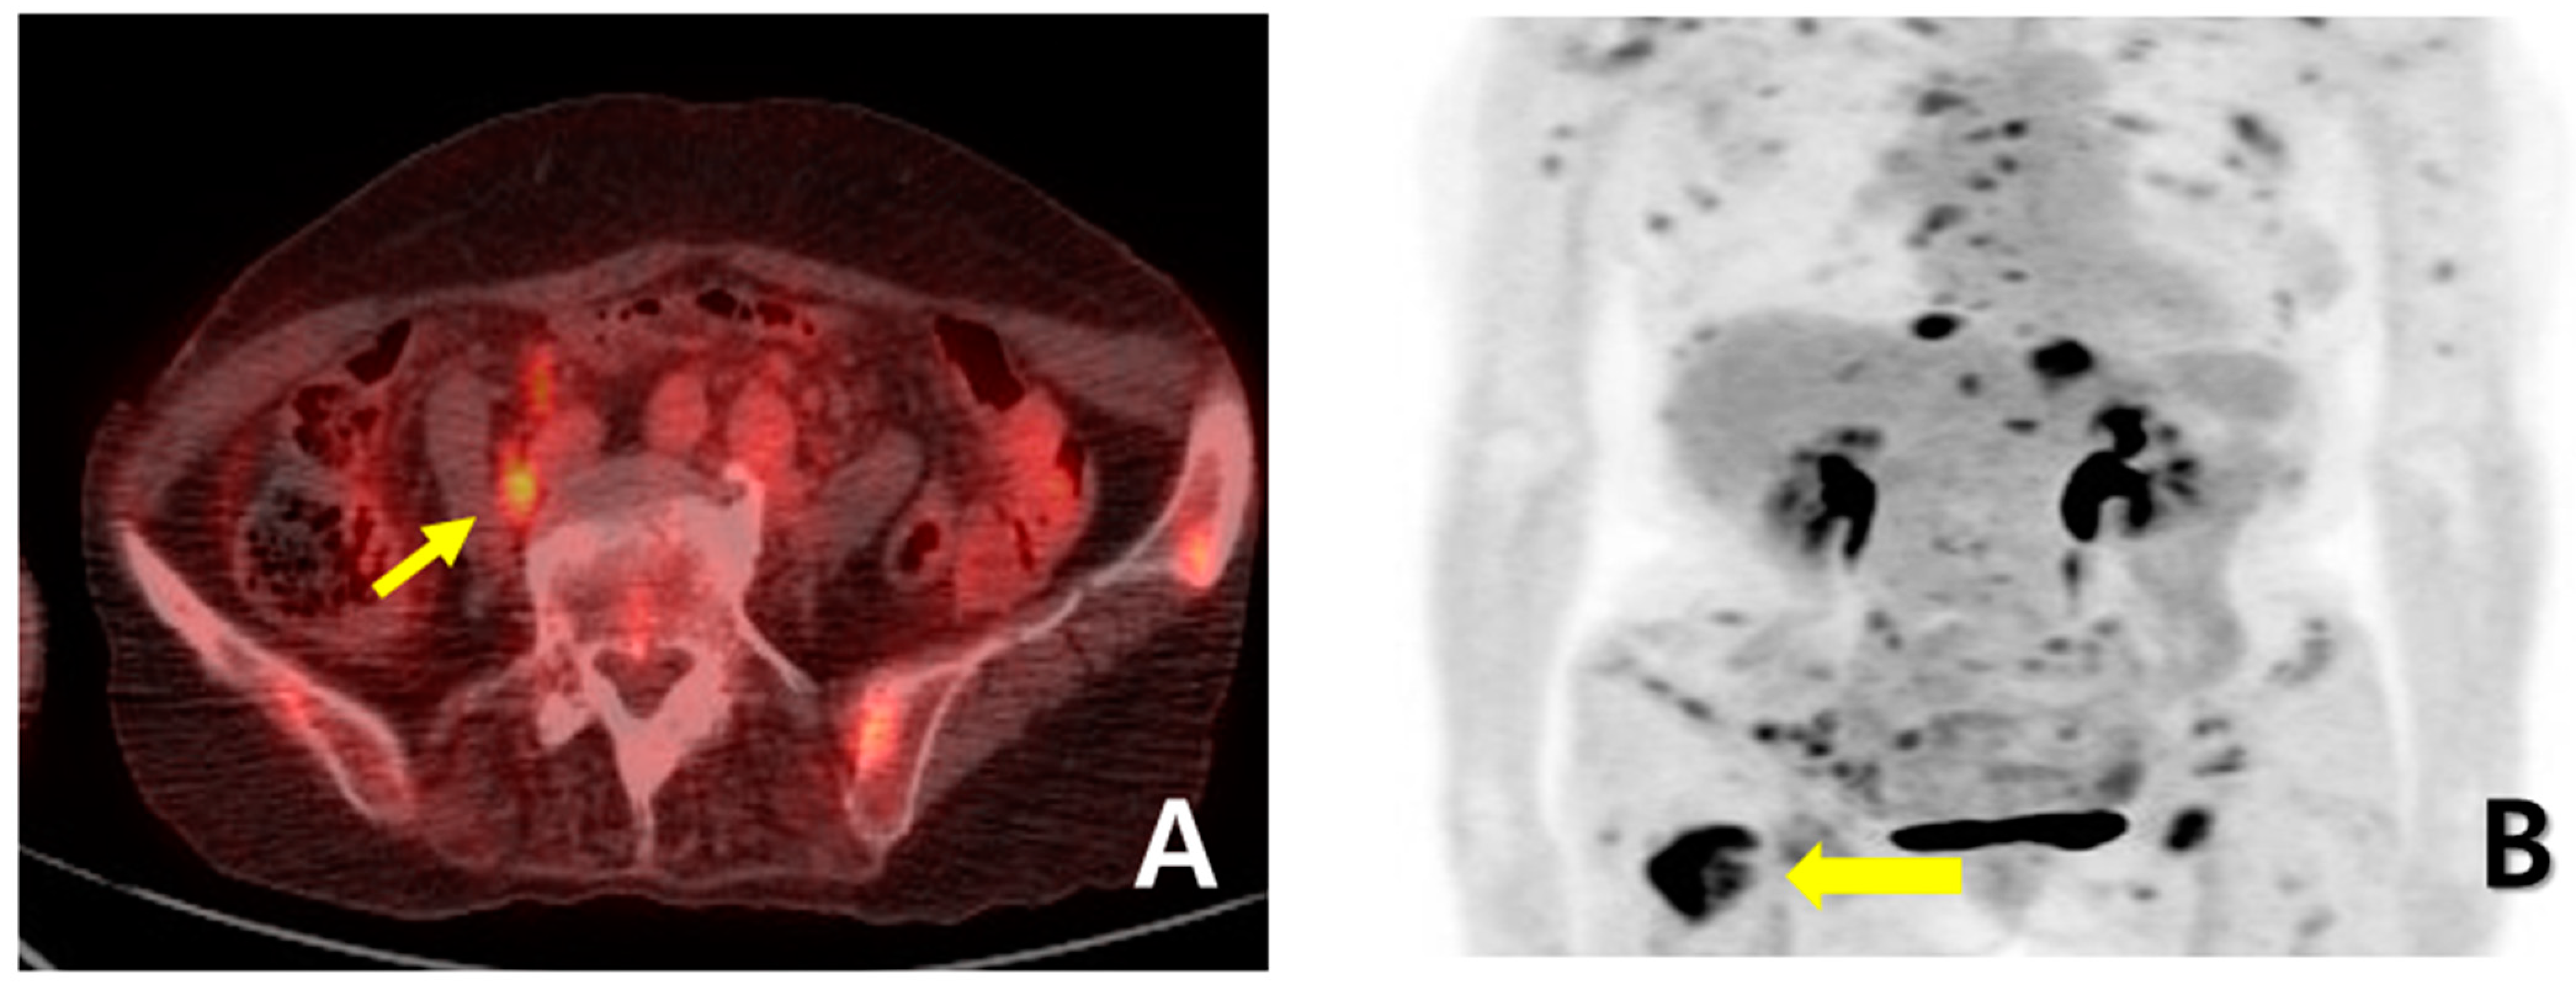

A 72-year-old female woman visited the outpatient clinic for rectal high-grade dysplasia detected during a screening test. She had a history of total thyroidectomy for thyroid cancer 25 years ago. She was admitted for endoscopic submucosal dissection for rectal cancer, and a mass in the right breast was observed during physical examination at admission. She received endoscopic submucosal dissection for rectal cancer, and ultrasonography-guided breast gun biopsy was performed during admission. On pathologic examination of the patient’s rectal cancer, the size of the tumor was 1 cm, and it was a moderately differentiated adenocarcinoma with mucosal invasion. She no longer received additional treatment for rectal cancer. During an ultrasonography examination of the right breast, a 4.9 × 4.4 × 2.2 cm irregular spiculated heterogenous echoic mass was observed. Pathologic examination revealed invasive ductal carcinoma, nuclear grade 2/3, and metastatic ductal carcinoma in the right axillary lymph node. Neoadjuvant chemotherapy, which was combined with Adriamycin, cyclophosphamide, and docetaxel, was performed. After four cycles of neoadjuvant chemotherapy, partial remission was observed. She underwent right modified radical mastectomy (MRM). Postoperative pathological examination revealed invasive ductal carcinoma, and pathologic stage ypT3(8 × 7 × 2.3 cm)ypN3(22/29). Immunohistochemical staining for estrogen receptor (ER), progesterone receptor (PR), and human growth factor receptor 2 (HER-2) were all negative (Figure 1A). After surgery, adjuvant chemotherapy based on capecitabine was performed along with radiation therapy. Nine months after MRM, gastroscopy was performed because of epigastric pain and discomfort. A gastroscopy revealed a 1 cm sized elevated mass in the posterior wall of the fundus, and endoscopic biopsy was performed (Figure 1B). Microscopic examination of the biopsy specimen showed solid nests or cords of tumor cells with histologic features resembling poorly differentiated carcinoma at initial diagnosis (Figure 1C). Immunohistochemical staining for GATA3 (GATA binding protein 3) and gross cystic disease fluid protein-15 (GCDFP-15) was carried out to rule out the possibility of metastatic breast cancer. Since both markers were negative in both breast cancer and in gastric cancer, it was inconclusive for determining the origin of the gastric tumor (Figure 2A–D). Moreover, the small size of the biopsy specimen itself brings limitations in evaluating the histologic features of entire gastric tumor. Therefore, a resection of the entire mass was needed. As the tumor cells were poorly differentiated, gastrectomy was considered more than endoscopic resection. Preoperative examination, including abdomen-pelvis CT and chest CT, was performed to check for distant metastasis, and no evidence of distant metastasis was found. She underwent totally laparoscopic total gastrectomy 10 months after MRM. The patient was diagnosed with T1bN1M0 gastric cancer according to AJCC 8th edition. Gross examination of the resected specimen revealed a well-demarcated mass measuring 1 × 0.7 cm. The entire mass was microscopically examined, and a poorly differentiated carcinoma that invaded the submucosa was identified; however, it differed from the general histological features of primary gastric adenocarcinoma for the following reasons: (1) No surface epithelial cells showed dysplasia or malignant change. (2) All tumor cells were located in the lamina propria with a solid nest or cord patterns with no glandular growth pattern (Figure 3A). Therefore, the tumor was more likely to be metastatic breast cancer than primary gastric cancer. It was reviewed again with the pathological findings of previous BC, and the histologic features of breast cancer and gastric cancer were almost identical. Additionally, cytokeratin CK 7 (CK7) immunostaining showed diffuse and strong positivity in both the gastric and breast specimens (Figure 3B,C). As a result, possible gastric metastasis of BC was diagnosed because the histological shape and immunohistochemical staining findings were consistent with BC. After the totally laparoscopic total gastrectomy, the patient received palliative first-line chemotherapy with paclitaxel and cisplatin (CDDP). Two months after gastrectomy, she was diagnosed with para-aortic lymph node metastasis and multiple bone metastases (Figure 4A,B). She underwent hip arthroplasty due to pathologic fracture of the right hip joint three months after gastrectomy, and she expired six months after gastrectomy.

Figure 4. (A) PET-CT performed two months after total gastrectomy showed para-aortic lymph node metastasis (yellow arrow); (B) PET-CT also showed multiple bone metastases (yellow arrow).